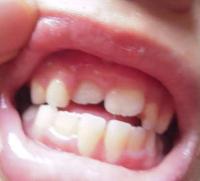

还有个造成牙齿不齐的情况就是乳牙还没掉,恒牙就长出来了。又要点名咱们家长了,要留意换牙时的时间和规律,并且孩子牙外伤和乳牙龋坏都不能不当回事哦~